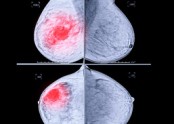

- ■ 정기적으로 유방촬영하는 것이 왜 중요할까요? ① 아래 환자분은 30대 중반에 검진상 양성 석회화가 있던 분으로 5년 되던 40세에 국가암 검진을 했고, 이때 과거에는 보이지 않던 소견으로 유방촬영 하부 작은 부위에 …

|